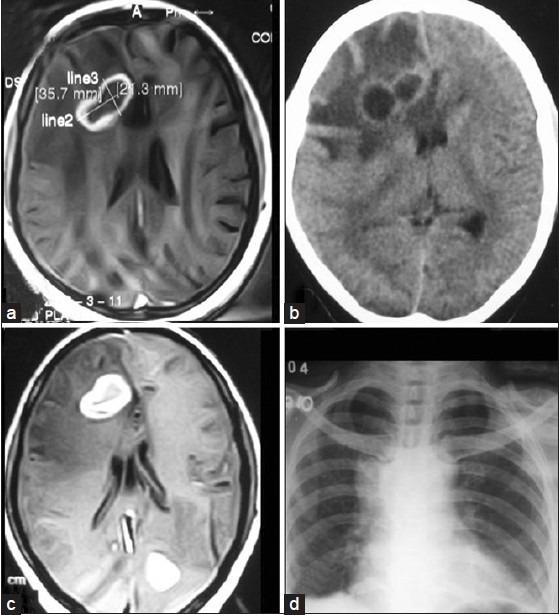

Aspergillosis of brain is very rare, and commonly seen in immunocompromised or immunosuppressed patient. Here, we report a cerebral aspergillosis condition in a late teen girl who is a Systemic Lupus Erythromatosis patient with steroid therapy. She developed headaches, vomitings, and convulsions. On the basis of clinical and neuroimaging, a diagnosis of cerebral tuberculoma was made, and she was put on anti-TB therapy, but she did not respond. Later, surgical partial excision biopsy confirmed the diagnosis. Her cerebral lesions responded with antifungal itraconazole therapy. The case will be presented with short literature review. Such a report in the literature is rare.

脑曲霉病非常罕见,常见于免疫功能低下或免疫抑制的患者。在此,我们报告一名十几岁晚期女孩的脑曲霉病病例,她是一名接受类固醇治疗的系统性红斑狼疮患者。她出现了头痛、呕吐和抽搐症状。基于临床和神经影像学检查,诊断为脑结核瘤,并给予抗结核治疗,但她没有反应。后来,手术部分切除活检确诊了病情。她的脑部病变对抗真菌药物伊曲康唑治疗有反应。该病例将结合简短的文献综述进行介绍。此类文献报道很少见。